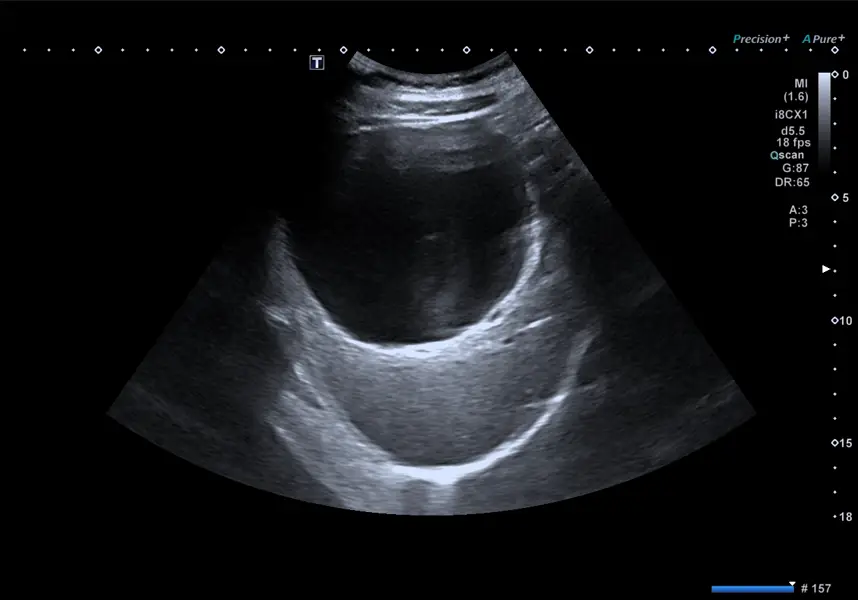

Investigations into bloating are based on the presumed diagnosis and likely cause, but typically involve an abdominal and pelvic ultrasound along with routine blood tests. Occasionally, a CT scan may be chosen over an ultrasound as the initial investigation if the history and clinical examination clearly indicate a disorder best assessed with a CT, or if the patient presents with constitutional symptoms or red flags such as significant appetite loss and unintentional weight loss over a short period. These signs may suggest the possibility of an underlying malignancy. An upper endoscopy and colonoscopy are also performed if a digestive cause is suspected, especially when the patient exhibits other high-risk symptoms such as passing blood, vomiting blood, persistent abdominal discomfort or pain, or a recent change in bowel habits.

Figure 14: An abdominal ultrasound shows a large liver cyst in a patient experiencing early satiety, epigastric discomfort, and bloating. Ultrasonography is a useful initial diagnostic tool in most cases due to its safety, lack of radiation, widespread availability, ease of use, and cost-effectiveness.